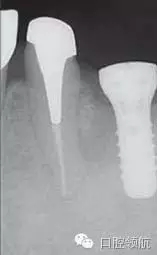

術后第18天,進行CBCT的確認(圖5),種植體周圍發(fā)現(xiàn)不透過影像,而且種植體有松動,因此在浸潤麻醉下拔除(圖6~圖8)。

圖5 術后18天CBCT的影像。